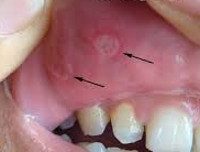

Хронический стоматит. Воспалительное поражение слизистой оболочки ротовой полости, имеющее длительное течение с периодическими ремиссиями и обострениями. В зависимости от клинической формы, хронический стоматит сопровождается ограниченным или диффузным покраснением слизистой оболочки, образованием в полости рта везикул или болезненных язв, повышенным слюноотделением, признаками общей интоксикации, регионарным лимфаденитом. Диагностика хронического стоматита включает исследование соскобов и ротовой жидкости (бактериологическое, цитологическое, ПЦР, биохимическое, иммунологическое), консультации стоматолога и тд специалистов. Лечение хронического стоматита предполагает устранение этиологических факторов, местную обработку полости рта, системную этиотропную терапию.

Хронический стоматит - различные по своему происхождению, рецидивирующие воспалительные процессы, поражающие слизистую оболочку полости рта. Наиболее частой клинической формой хронического стоматита служит рецидивирующий афтозный стоматит: среди различных заболеваний слизистой оболочки полости рта на его долю приходится 5% случаев. По типу хронического стоматита может протекать рецидивирующий герпетический стоматит, язвенно-некротический стоматит Венсана, протезный стоматит, стоматит курильщиков, грибковый стоматит и тд В большинстве случаев развитие хронического стоматита связано не только с местными факторами, но и с нарушениями работы различных систем организма, что делает данное заболевание актуальным как для стоматологии, так и для иммунологии, гастроэнтерологии, эндокринологии, отоларингологии.